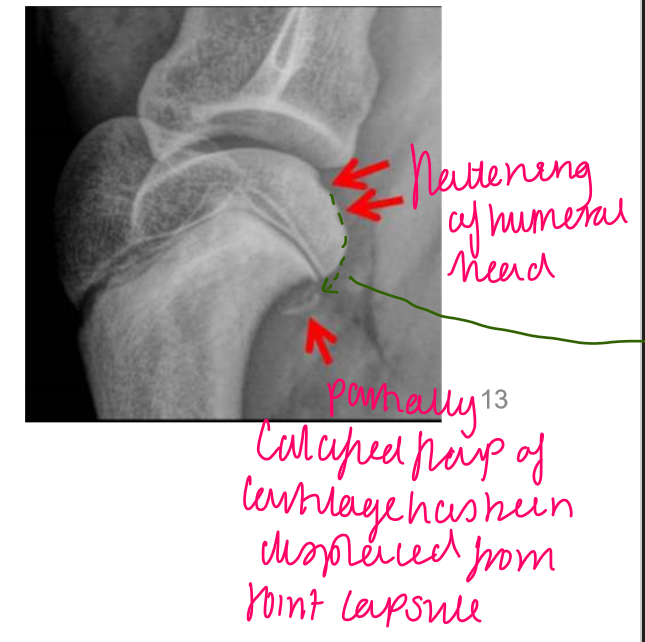

Osteochondrosis

-Red arrows show disc like depressions

What will osteochondrosis (developmental) present as?

Loss of rounded contour of caudal surface of humeral head

Radiolucent defect

May have surrounding sclerosis

May have calcified free body in joint

label

flattened/ indent of the humeral head

partially calcified flap of cartilage → displaced from joint capsule